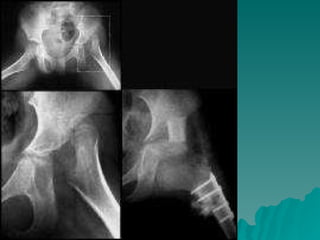

Developmental dysplasia of the hip is a condition where the hip joint is unstable or partially dislocated. It affects 1-50 out of every 1000 live births, with 60% being detected by 1 week of age and 90% by 8 weeks. The document discusses the anatomy, aetiology, pathology, clinical features, imaging, and different treatment approaches depending on if the patient is under 6 months, 6 months to 6 years, or above 6 years of age.